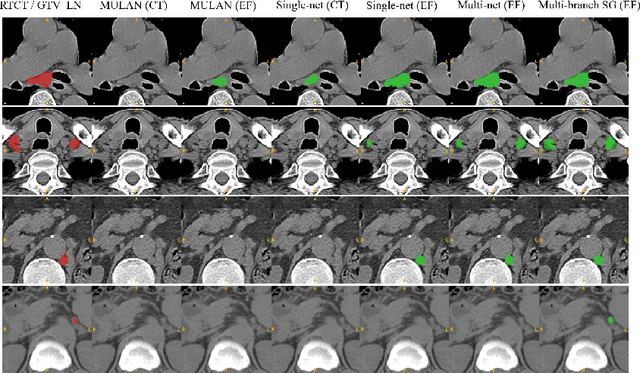

Abstract:Determining the spread of GTV$_{LN}$ is essential in defining the respective resection or irradiating regions for the downstream workflows of surgical resection and radiotherapy for many cancers. Different from the more common enlarged lymph node (LN), GTV$_{LN}$ also includes smaller ones if associated with high positron emission tomography signals and/or any metastasis signs in CT. This is a daunting task. In this work, we propose a unified LN appearance and inter-LN relationship learning framework to detect the true GTV$_{LN}$. This is motivated by the prior clinical knowledge that LNs form a connected lymphatic system, and the spread of cancer cells among LNs often follows certain pathways. Specifically, we first utilize a 3D convolutional neural network with ROI-pooling to extract the GTV$_{LN}$'s instance-wise appearance features. Next, we introduce a graph neural network to further model the inter-LN relationships where the global LN-tumor spatial priors are included in the learning process. This leads to an end-to-end trainable network to detect by classifying GTV$_{LN}$. We operate our model on a set of GTV$_{LN}$ candidates generated by a preliminary 1st-stage method, which has a sensitivity of $>85\%$ at the cost of high false positive (FP) ($>15$ FPs per patient). We validate our approach on a radiotherapy dataset with 142 paired PET/RTCT scans containing the chest and upper abdominal body parts. The proposed method significantly improves over the state-of-the-art (SOTA) LN classification method by $5.5\%$ and $13.1\%$ in F1 score and the averaged sensitivity value at $2, 3, 4, 6$ FPs per patient, respectively.

Abstract:Finding, identifying and segmenting suspicious cancer metastasized lymph nodes from 3D multi-modality imaging is a clinical task of paramount importance. In radiotherapy, they are referred to as Lymph Node Gross Tumor Volume (GTVLN). Determining and delineating the spread of GTVLN is essential in defining the corresponding resection and irradiating regions for the downstream workflows of surgical resection and radiotherapy of various cancers. In this work, we propose an effective distance-based gating approach to simulate and simplify the high-level reasoning protocols conducted by radiation oncologists, in a divide-and-conquer manner. GTVLN is divided into two subgroups of tumor-proximal and tumor-distal, respectively, by means of binary or soft distance gating. This is motivated by the observation that each category can have distinct though overlapping distributions of appearance, size and other LN characteristics. A novel multi-branch detection-by-segmentation network is trained with each branch specializing on learning one GTVLN category features, and outputs from multi-branch are fused in inference. The proposed method is evaluated on an in-house dataset of $141$ esophageal cancer patients with both PET and CT imaging modalities. Our results validate significant improvements on the mean recall from $72.5\%$ to $78.2\%$, as compared to previous state-of-the-art work. The highest achieved GTVLN recall of $82.5\%$ at $20\%$ precision is clinically relevant and valuable since human observers tend to have low sensitivity (around $80\%$ for the most experienced radiation oncologists, as reported by literature).

Abstract:Finding and identifying scatteredly-distributed, small, and critically important objects in 3D oncology images is very challenging. We focus on the detection and segmentation of oncology-significant (or suspicious cancer metastasized) lymph nodes (OSLNs), which has not been studied before as a computational task. Determining and delineating the spread of OSLNs is essential in defining the corresponding resection/irradiating regions for the downstream workflows of surgical resection and radiotherapy of various cancers. For patients who are treated with radiotherapy, this task is performed by experienced radiation oncologists that involves high-level reasoning on whether LNs are metastasized, which is subject to high inter-observer variations. In this work, we propose a divide-and-conquer decision stratification approach that divides OSLNs into tumor-proximal and tumor-distal categories. This is motivated by the observation that each category has its own different underlying distributions in appearance, size and other characteristics. Two separate detection-by-segmentation networks are trained per category and fused. To further reduce false positives (FP), we present a novel global-local network (GLNet) that combines high-level lesion characteristics with features learned from localized 3D image patches. Our method is evaluated on a dataset of 141 esophageal cancer patients with PET and CT modalities (the largest to-date). Our results significantly improve the recall from $45\%$ to $67\%$ at $3$ FPs per patient as compared to previous state-of-the-art methods. The highest achieved OSLN recall of $0.828$ is clinically relevant and valuable.